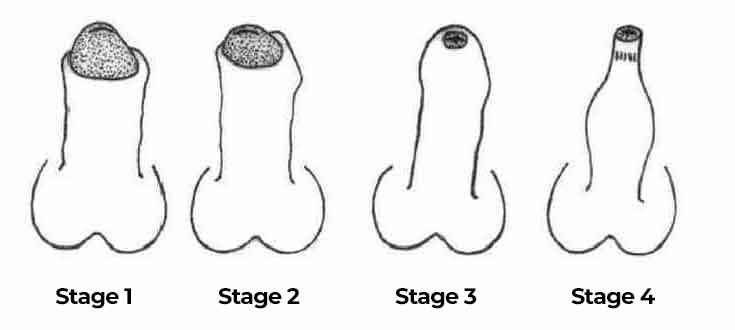

Age-related reduction (atrophy) of the penis

Statistics show that 80% of men are dissatisfied with the size of their reproductive organ. But after age 35, men face a much more severe problem: age-related loss of muscle tissue, 2-3% annually. Unfortunately, this problem also affects the penis, which is 50% composed of smooth muscle. Over the years, the penis begins to shrink:

If you have a small penis, you will not satisfy a woman and will never bring her to orgasm! This is a proven fact! Deal with this now, before it's too late! I'll tell you how you can avoid age-related penile atrophy.